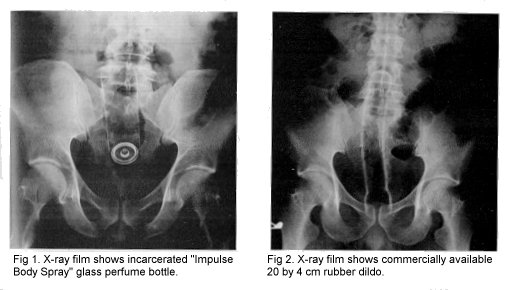

• Impulse Body Spray, Dildo (authentic)

Case 1. A 39-year-old married white male lawyer presented with a self- inserted perfume bottle in his rectum that he was unable to remove using various objects, including a back scratcher. He had inserted this bottle on previous occasions. Edema of the rectum and sigmoid colon precluded the successful manual removal of the object in the emergency room. A pelvic x-ray film (Fig.1) showed the object to be lodged 12 cm proximal to the dentate line. The 3 by 17 cm object, "Impulse Body Spray," was removed manually after a spinal anesthetic. The patient was discharged on the second postoperative day. He refused psychologic counseling.

Case 2. A 39-year-old white male was admitted to the University Hospital psychiatric service for evaluation of a 2-week history of bloody diarrhea and auditory hallucinations. Rectal examination revealed a foreign body approximately 3 cm above the anal verge. An x- ray film (Fig. 2) showed that it was 20 cm in length. The object could not be removed by manual or endoscopic means. The patient consented to extraction of the dildo under general anesthetic. Biopsy specimens of the hemorrhagic rectal mucosa were performed and were negative on Ziehl-Neelson stains for mycobacterial or cryptosporidium infection. The patient was discharged without complications the following day.

xrays 29K jpg

(thanx to Thomas Comegys for scanning prowess)